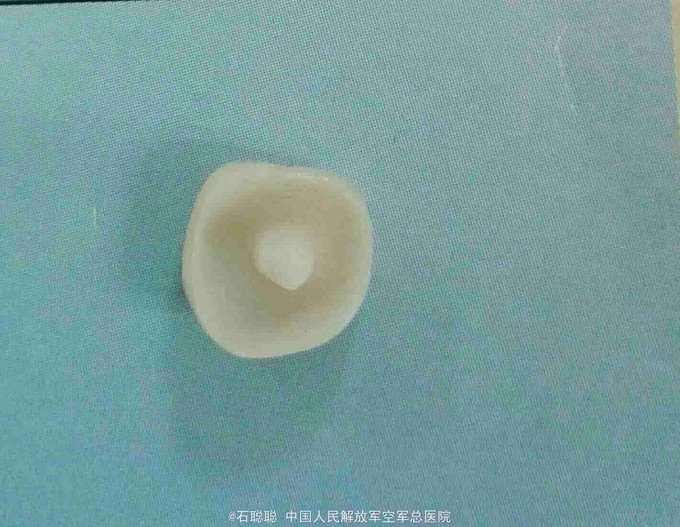

右下7全瓷嵌体冠修复

诊断:47牙体缺损 治疗计划:47全瓷嵌体冠修复 处置:47去除暂封,磷酸锌垫底,光固化覆合树脂充填,预备全瓷嵌体冠,取模,比色3M2,制作临时冠,调合,磨光,粘固 一周后复诊: 检查:临时冠完整在位,无松动,叩痛- 处置:去除47临时冠,试戴全瓷嵌体冠,调合,抛光,U200粘接 医嘱:勿用患牙咀嚼脆骨、坚果等过硬食物 口腔卫生宣教:巴斯刷牙法,牙线使用方法 不适复诊

讨论:这是常一例规的后牙根管治疗后要求修复的病历,患牙的对合略有伸长,咬合紧,尽管将对合做了降合处理,仍会降低龈合距离,削弱全冠的固位力,幸运的是47的四个轴壁均完整并且高度、厚度能满足制作嵌体冠的需要,可以利用髓腔制备固位形,明显改善了固位不足的状态。嵌体预备要点要满足轴壁无倒凹,有2-5度的合方外展,与牙冠就位道一致。